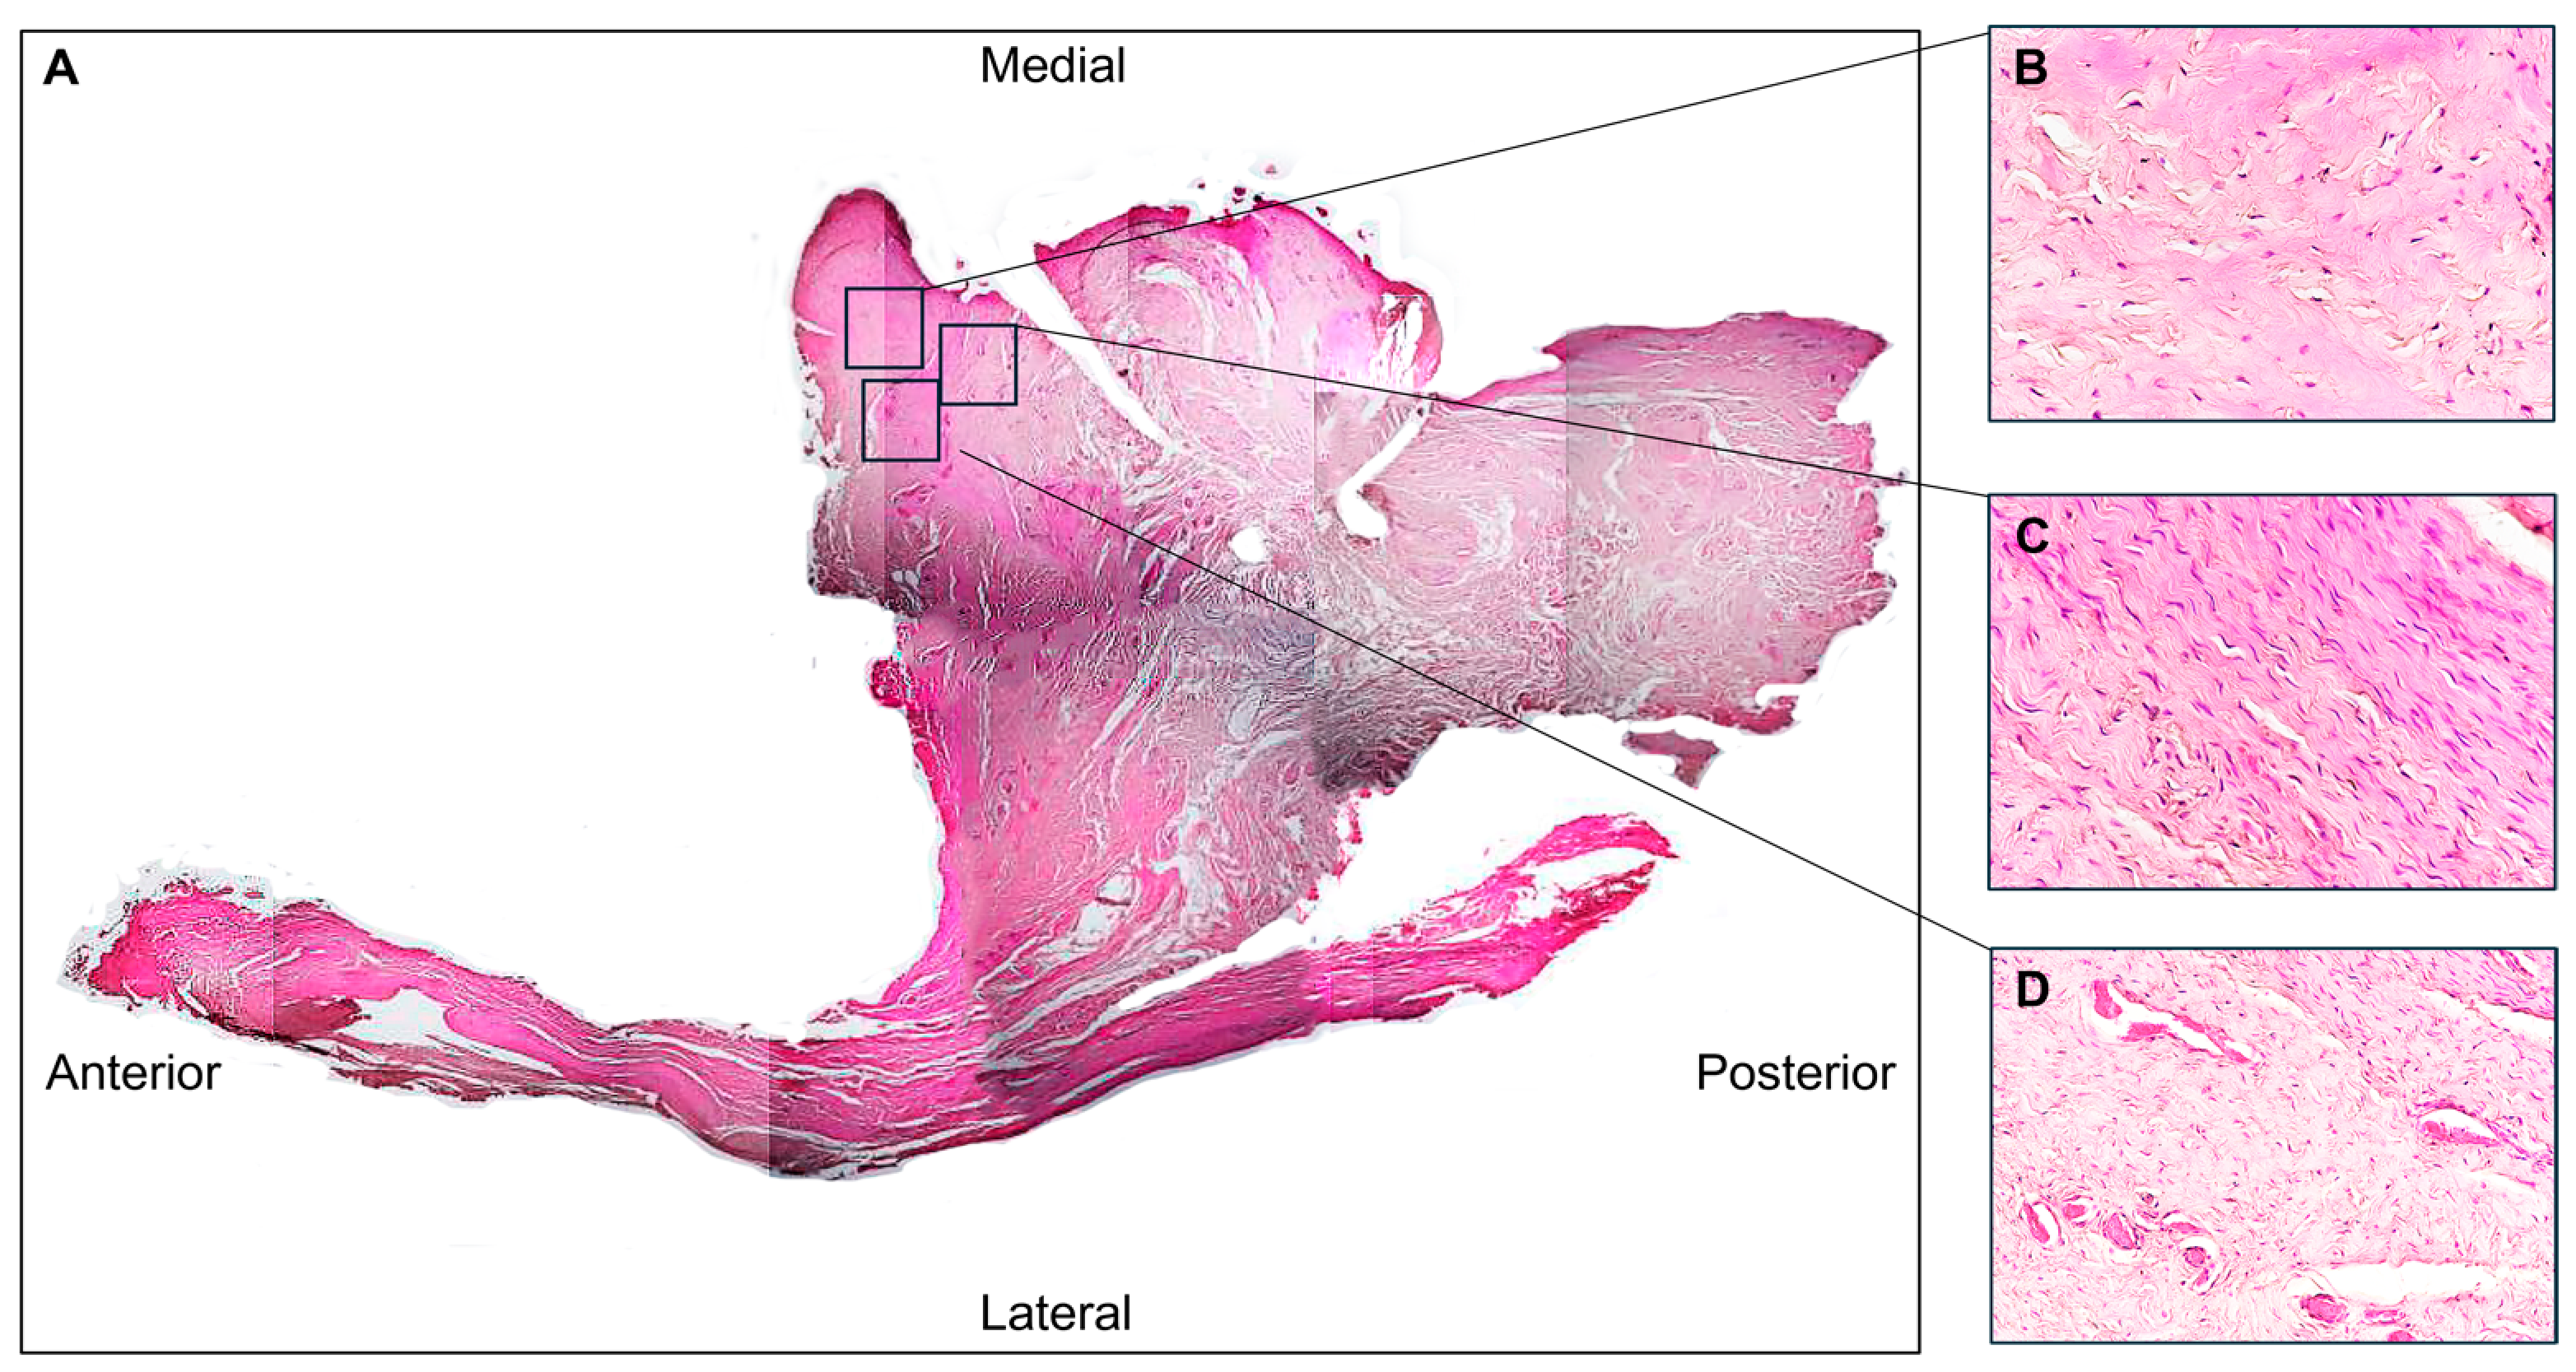

3.1. Histological Evaluation